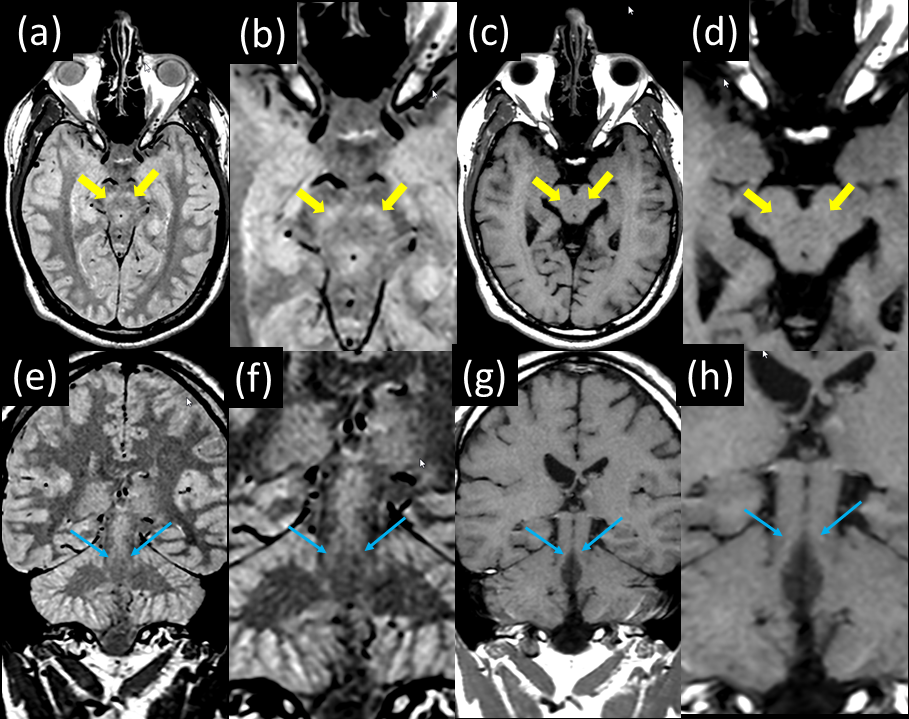

T1 mapping clearly demonstrates both elevated T1 and PD in the SN and LC compared to surrounding tissue [Fig 1]. The mean T1 value from manually drawn ROIs within the left and right substantia nigra over 2 subjects was 714 +/- 68 ms and in the locus coeruleus was 830 +/- 38 ms. This is substantially higher than the mean T1 value from ROIs in myelinated tissue neighboring the SN (572 +/- 40 ms). Thin section, PD-weighted, FSE shows clear, hyperintense signal in the SN and LC [Fig 2] whereas the T1-weighted FSE variant does not clearly visualize the SN and LC. The LC was consistently depicted in all 3 subjects and is well visualized in coronal PD-weighted FSE images [Fig 3].

Figure 1: T1 mapping results in neuromelanin containing structures. Quantitative T1 maps (a-c) and proton density (PD) maps (d-f) are shown. Clear depiction of the SN (yellow arrows) in Axial images in both T1 (a) and PD (d) maps are seen. Depiction of the LC (blue arrows) in Axial (b, e) and Coronal (c, f) reformatted images in both the T1 (b, c) and PD (e, f) maps are seen.